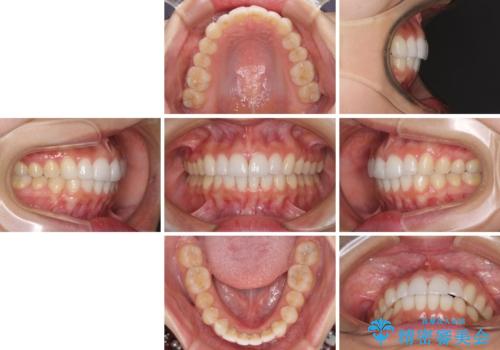

口が閉じにくい 1本飛び出した前歯の矯正治療

- 1本飛び出した前歯を治したいとのことで来院された患者様です。

歯列全体の拡大とIPR(歯と歯の間を削る)によってデコボコが解消するようにし、さらにゴムかけを活用して右側の咬み合わせ位置を変えるように設計し、インビザラインにより治療を行うこととしました。

結婚式までに前歯を整えたいとのことでしたが、インビザラインでは先に奥歯を移動させてから前歯を動かすため、間に合わない可能性がありました。しかし、結婚式までに期間があったことと、マウスピースをしっかりと装着してくださったことで、十分な歯列に整えることができました。